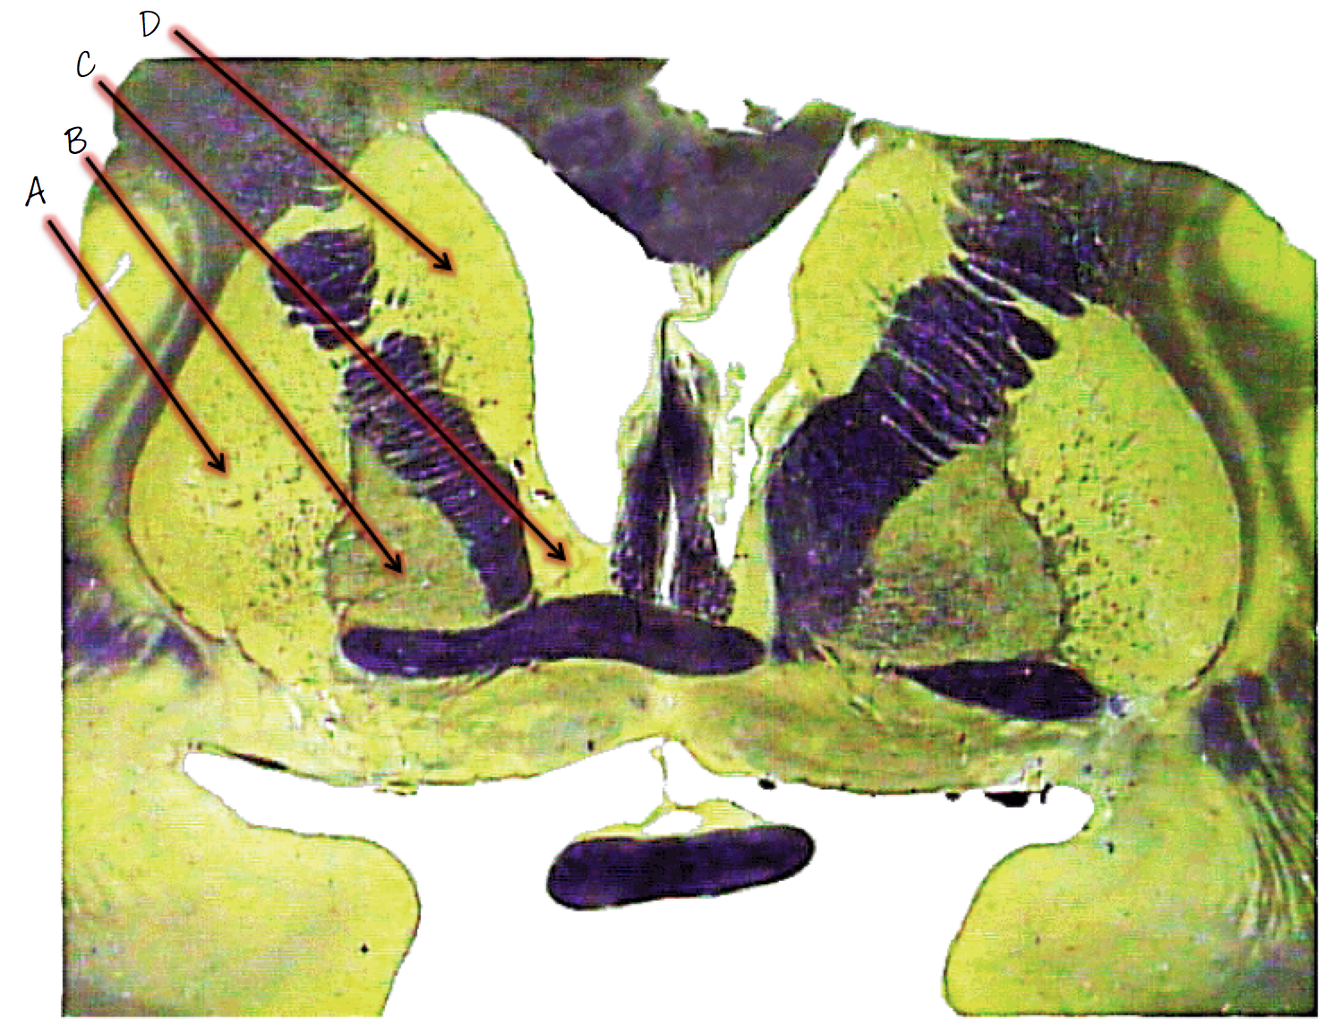

A; internal capsule

B; external capsule

C; extreme capsule

D; claustrum